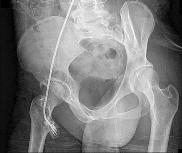

Question 1:

A 25-year-old male sustains a high-energy Pauwels type III femoral neck fracture. In a young adult with this vertical fracture pattern, which of the following internal fixation constructs biomechanically offers the greatest resistance to vertical shear forces and varus collapse?

Correct Answer: Sliding hip screw with a supplemental derotational screw

Pauwels type III femoral neck fractures have a vertical orientation (>50 degrees) and are subjected to high shear forces rather than compressive forces. Biomechanical studies have consistently demonstrated that a fixed-angle device, such as a sliding hip screw (SHS) with a supplemental derotational screw, provides superior stability against vertical shear and varus collapse compared to multiple cancellous screws in these specific high-angle fractures.